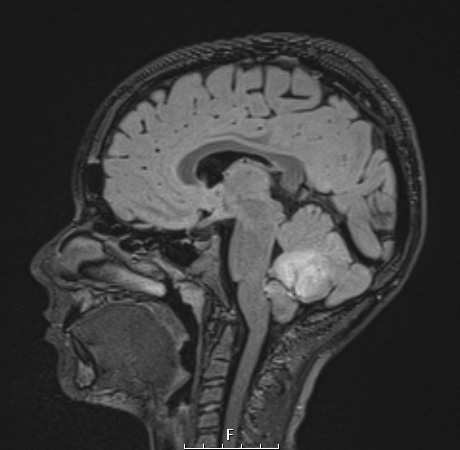

Case 1 History ---- The patient is an 11-year-old boy with a posterior fossa mass. Operative procedure: Craniotomy for tumor resection. ---- 1A1 This FLAIR MRI with applied contrast demonstrates a hyperintense mass in the posterior fossa involving the cerebellum.